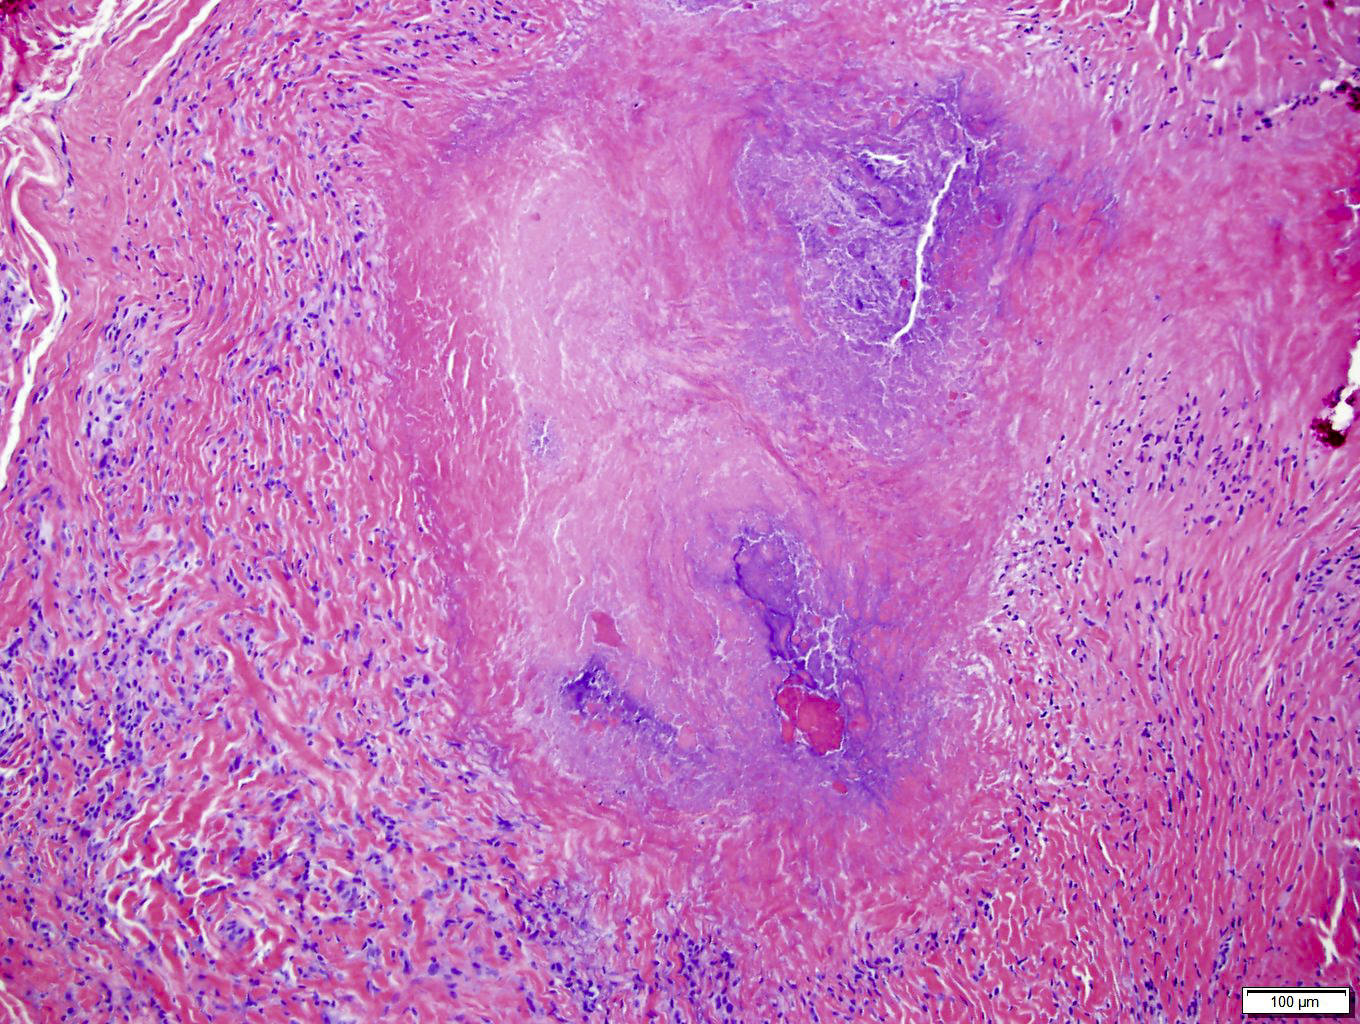

Rheumatoid Arthritis Histology Arthritis Skin Nodules Rheumatoid nodules are firm lumps that develop under the skin. This includes nodules, rashes, sores,. Rheumatoid nodules are firm lumps under the skin. They generally form on or. They are common in rheumatoid arthritis (ra) and usually occur near the affected joints, such as the. They appear on fingers, knuckles, elbows, forearms, and knees. Rheumatoid nodules are firm, noticeable lumps. Arthritis Skin Nodules.

Rheumatoid Nodule Histology Arthritis Skin Nodules Rheumatoid arthritis (ra) can cause a rash, hives, or other skin problems like firm lumps called rheumatoid nodules. They appear on fingers, knuckles, elbows, forearms, and knees. These bumps can be as large as a. Rheumatoid nodules are firm, noticeable lumps that form underneath the skin of some rheumatoid arthritis patients. They generally form on or. They are common in. Arthritis Skin Nodules.